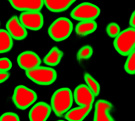

The task of nuclei segmentation can be roughly divided into two stages: the first stage is extracting the foreground(nuclei), the second stage is segmenting the connected foreground area into separated nuclei and finding out the boundary of each nucleus. Our method intends to merge these two steps by extracting the nuclei and their edges at the same time. That is the reason why it is named ”nuclei-boundary(NB) model”. As shown in Fig.3, the output of the NB model has three channels, each has the same height and width with the input image. Its values represent the probabilities of each pixel being background𝑏𝑎𝑐𝑘𝑔𝑟𝑜𝑢𝑛𝑑background, boundary𝑏𝑜𝑢𝑛𝑑𝑎𝑟𝑦boundary or inside𝑖𝑛𝑠𝑖𝑑𝑒inside class, respectively. The manual annotation for our segmentation problem is the boundary of each nucleus. A pixel belonging to the boundary𝑏𝑜𝑢𝑛𝑑𝑎𝑟𝑦boundary class means that it is on or inside an annotated boundary and within 2 pixel from the boundary. Pixels of the inside𝑖𝑛𝑠𝑖𝑑𝑒inside class are those that are inside annotated boundary but are not boundary𝑏𝑜𝑢𝑛𝑑𝑎𝑟𝑦boundary pixels. Correspondingly, the output can be regarded as an RGB image and the estimated maps of the background𝑏𝑎𝑐𝑘𝑔𝑟𝑜𝑢𝑛𝑑background, boundaries𝑏𝑜𝑢𝑛𝑑𝑎𝑟𝑖𝑒𝑠boundaries and nuclei𝑛𝑢𝑐𝑙𝑒𝑖nuclei are represented by red, green and blue, respectively, as shown in Fig.3. To generate the ternary mask for training, we apply a morphology operator to each nucleus to obtain the inside𝑖𝑛𝑠𝑖𝑑𝑒inside pixels, and then subtract inside𝑖𝑛𝑠𝑖𝑑𝑒inside pixels from the nucleus to get boundary𝑏𝑜𝑢𝑛𝑑𝑎𝑟𝑦boundary pixels.

Figure 6 shows how our method segments the nuclei step by step. The color variety is well controlled by the color normalization procedure. The prediction result shows clear nuclear areas and nucleus boundaries. In the final segmentation result and ground truth image, each nucleus is represented by a different color.

Figure 6: (a) examples of original histopathology images; (b) corresponding images after color normalization. (c) raw segmentation results by our algorithm. (d) final segmentation result.